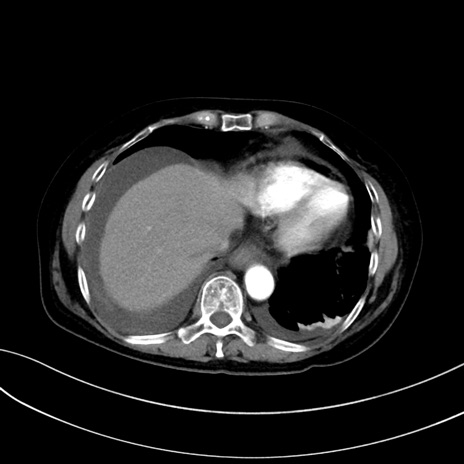

症例13 CT(横断像)1日半後